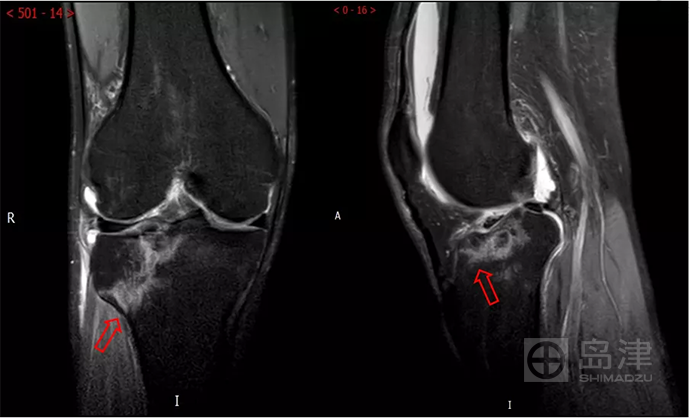

45岁男性,与孩子玩耍时,从一级台阶上蹦下即感右膝疼痛明显,无法行走。

右膝正侧位X线:未见骨折直接及间接征象 。

DTS 显示胫骨平台骨折 。

查 CT MR ,与DTS结果一致。

右胫骨平台隐匿性骨折

CT结果与DTS一致

MRI结果与DTS一致